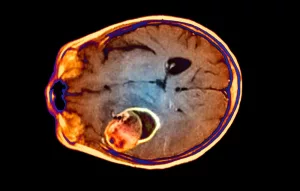

How a Concussion Affects Your Brain

What actually happens after a mild traumatic brain injury

When a sudden blow or jolt makes your brain slam against the skull, a cascade of microscopic changes erupts. Neurons get stretched, a brief swelling (edema) swells, and the delicate balance of neurotransmitters goes haywire. Think of it as a tiny earthquake inside your head that rattles the wiring.

Why the brain is extra sensitive to toxins

During recovery the blood‑brain barrier is still mending, making it easier for substances like ethanol (the alcohol in your drinks) to slip through and interfere with neural repair. According to Dr. Mark Heisig, “your tolerance for alcohol drops dramatically after a concussion, so what used to be one drink might feel like two.”